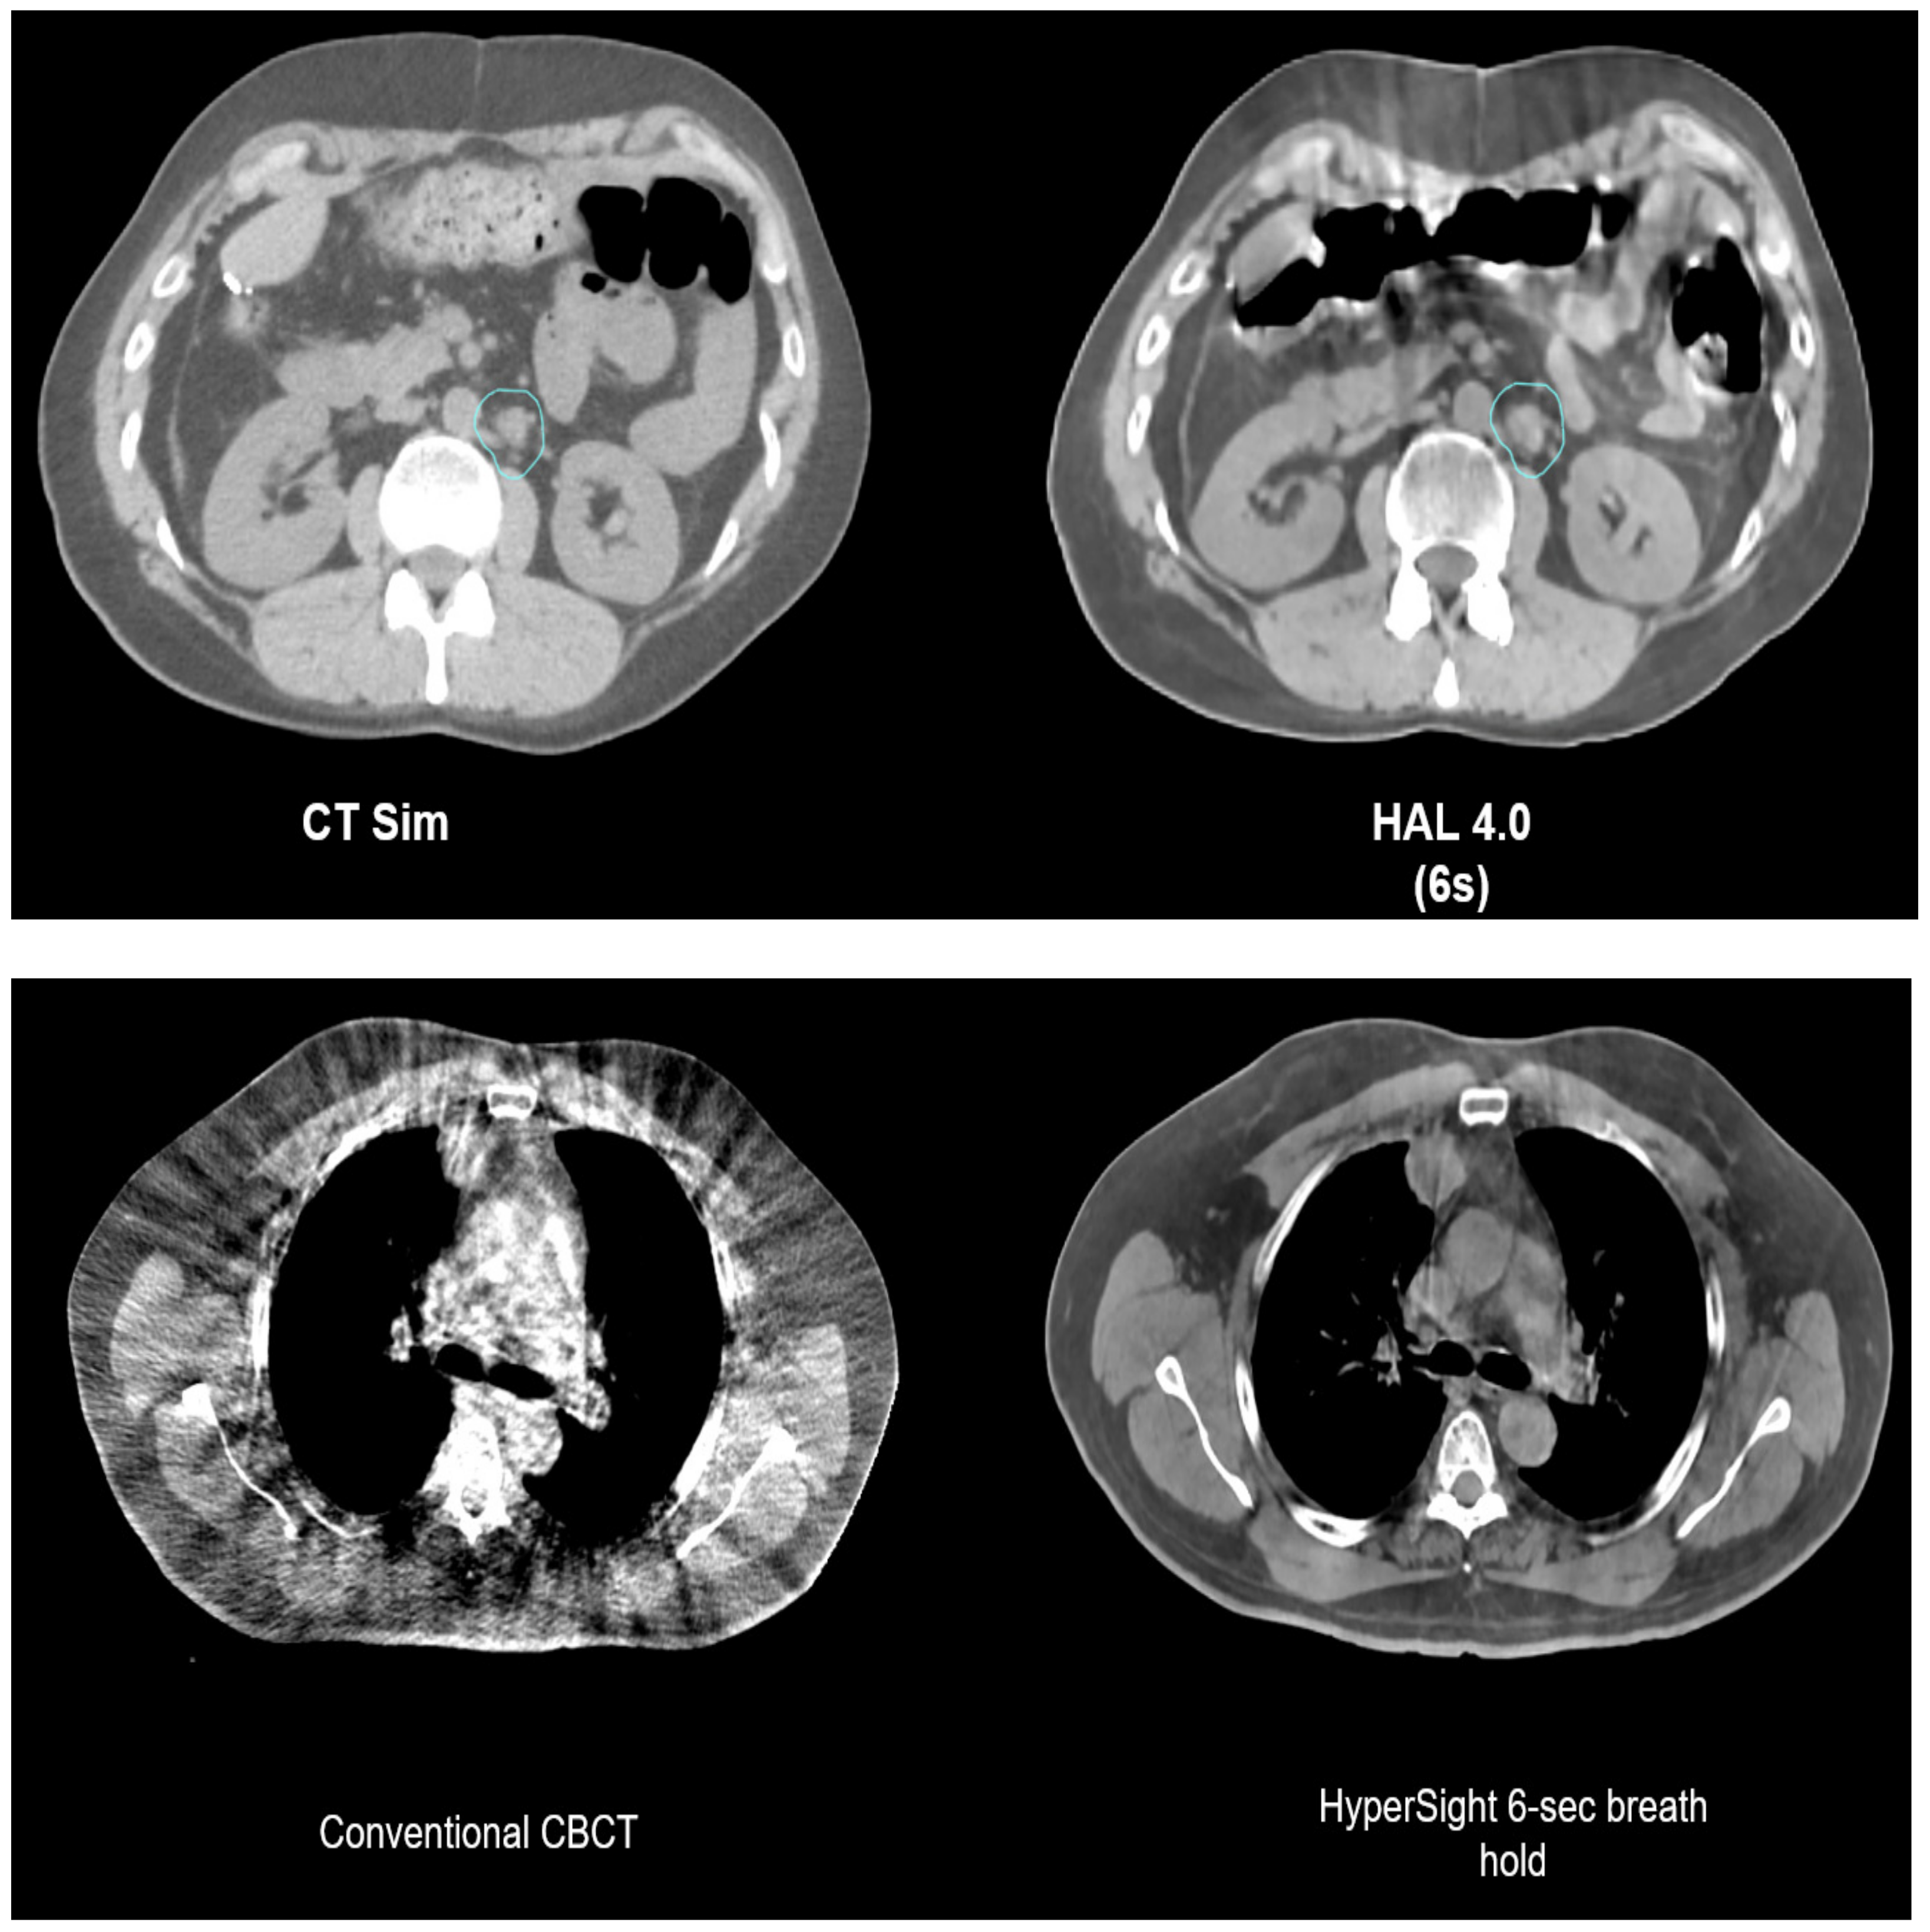

4.2. CBCT-Based Online ART

- Liu, H.; Schaal, D.; Curry, H.; Clark, R.; Magliari, A.; Kupelian, P.; Khuntia, D.; Beriwal, S. Review of cone beam computed tomography based online adaptive radiotherapy: Current trend and future direction. Radiat. Oncol. 2023, 18, 144. [Google Scholar] [CrossRef] [PubMed]

- O’Hara, C.J.; Bird, D.; Al-Qaisieh, B.; Speight, R. Assessment of CBCT–based synthetic CT generation accuracy for adaptive radiotherapy planning. J. Appl. Clin. Med. Phys. 2022, 23, S342–S343. [Google Scholar] [CrossRef] [PubMed]

- Schiff, J.P.; Price, A.T.; Stowe, H.B.; Laugeman, E.; Chin, R.-I.; Hatscher, C.; Pryser, E.; Cai, B.; Hugo, G.D.; Kim, H.; et al. Simulated computed tomography-guided stereotactic adaptive radiotherapy (CT-STAR) for the treatment of locally advanced pancreatic cancer. Radiother. Oncol. 2022, 175, 144–151. [Google Scholar] [CrossRef] [PubMed]